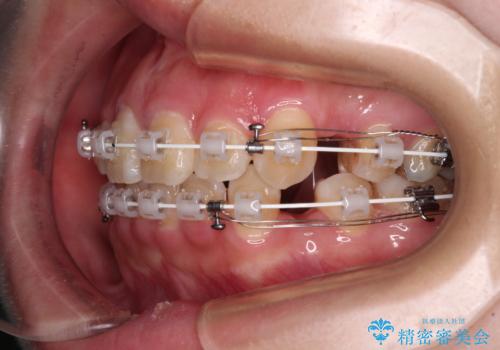

- 審美装置

- 1年7ヶ月

スペースを閉じるステージでの移動がとても早く、1年半ほどで終えることができました。

唇が引っかかる感触もなくなり、口が閉じやすくなりました。